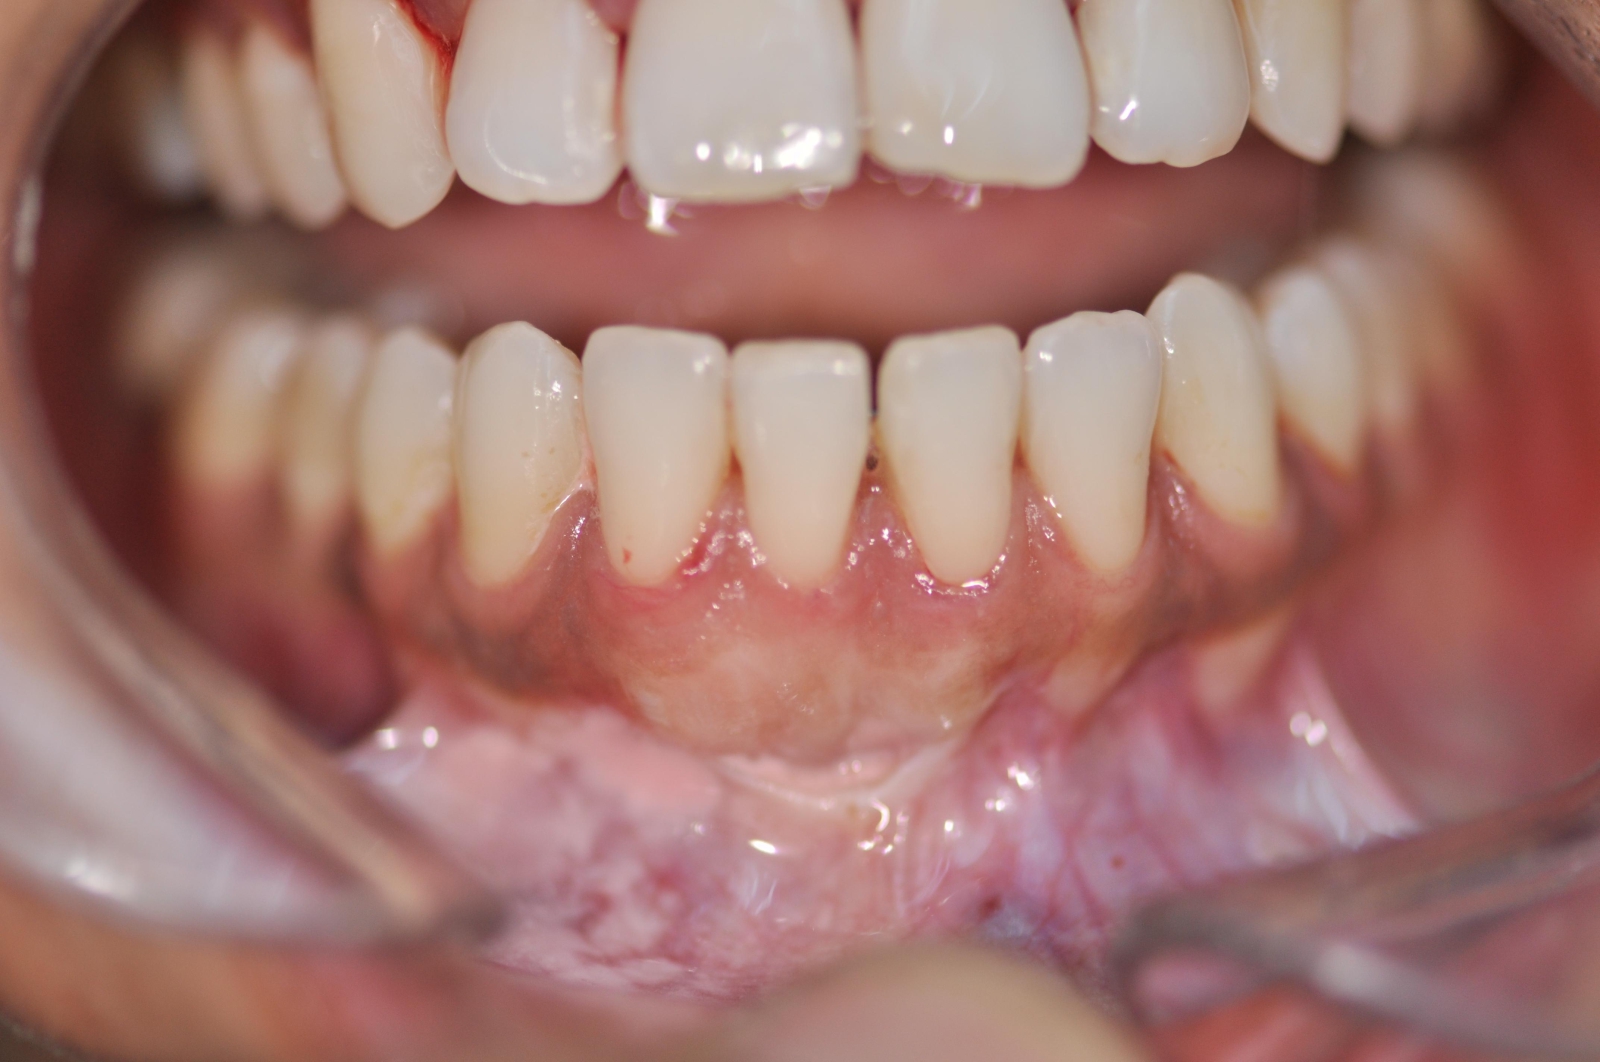

Chirurgie de "sourire Gingivales" ou "Gummy Smile"

Le sourire gingival est appelé Gummy Smile. Il s’agit d’une situation lors de laquelle la gencive descend trop bas sur les couronnes des dents, soit les parties qui sont normalement visibles lorsqu’on sourit.

Cela se traduit par des gencives proéminentes et des dents qui semblent plus courtes. Bien entendu, cela nuit à l’apparence du sourire.